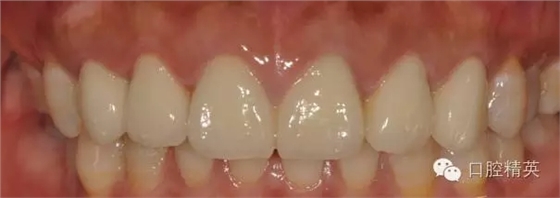

修復(fù)體完成后正面觀

640.webp (18).jpg